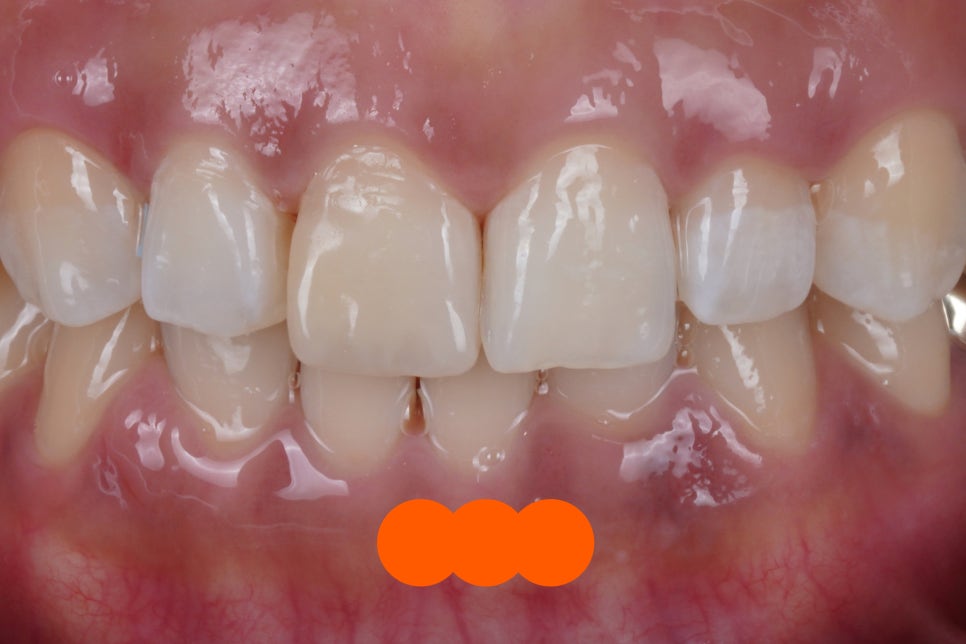

그 결과, 이렇게 자연스럽게 되었어요.

앞니는 제가 유명해진 이유이자 잘하는 진료인

Direct Composite Veneer 입니다.

역시나 자연치아가 가진

고유의 그라데이션

<투명층>도 재현해드렸습니다.

치아 사이즈도 잘 맞춰 드렸고요.